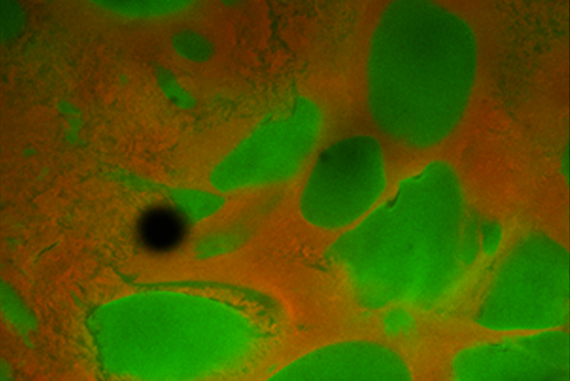

In this image, new bone structure has formed after stem cells were transplanted using the novel hydrogel strategy developed at the Wyss Institute and described in the Sept. 14 issue of Nature Materials.

Courtesy of the Wyss Institute at Harvard University

By coupling the bulk gel with a small “peptide” derived from the extracellular environment of genuine stem cell niches, and mixing it with a tissue-specific stem cell type as well as the porogen, the team can create a bone-forming artificial niche. While the bulk gel provides just the right amount of elasticity plus a relevant chemical signal to coax stem cells to proliferate and mature, the porogen gradually breaks down, leaving open spaces into which the stem cells expand before they naturally migrate out of the gel structure altogether to form actual mineralized bone tissue.

In small-animal experiments conducted so far, the researchers show that a void-forming hydrogel with the correct chemical and elastic properties provides better bone regeneration than transplanting stem cells alone. Of further interest, the maturing stem cells deployed by the hydrogel also induce nearby native stem cells to contribute to bone repair, further amplifying their regenerative effects.